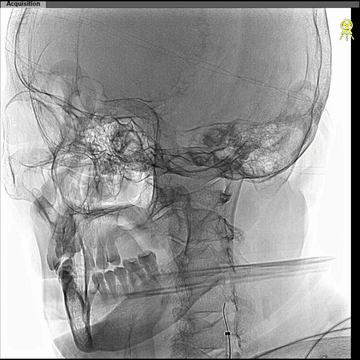

CTA:左ICA起始部重度狭窄,左CCA与无名动脉短共干,左CCA起始段走行明显向左,与主动脉弓呈显著锐角。

西蒙管于左CCA造影,用硬泥鳅导丝超选入枕动脉,并西蒙管前推上高到枕动脉,加强上支撑,后长鞘顺利过弓,抵达左CCA远端。

建立治疗通路后,保护伞下(NAV6 4-7mm)行左侧ICA起始部狭窄支架植入(wallstent 9*40mm)。